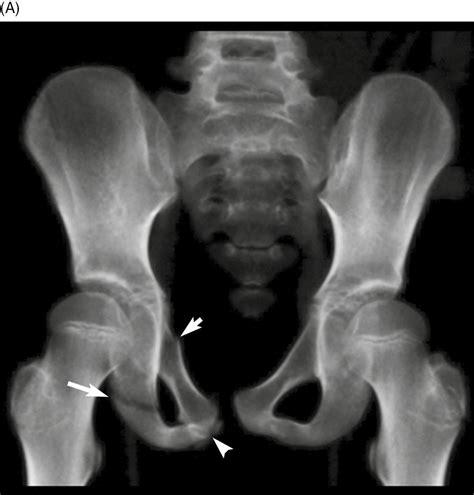

A Bucket Handle Fracture is a specific type of fracture where a segment of bone is displaced, often in a manner that resembles the handle of a bucket. This type of fracture is commonly seen in the knee, particularly in the medial meniscus, but can also occur in other joints. The fracture typically involves a longitudinal split in the bone, with the displaced segment often remaining attached to the surrounding ligaments or tendons.

• Imaging Tests: X-rays, MRI, or CT scans to visualize the fracture and determine the extent of the damage.

Imaging tests are crucial for confirming the diagnosis and planning the appropriate treatment. X-rays can show the fracture line, while MRI and CT scans provide detailed images of the soft tissues and bone structure.

• bucket handle fracture pelvis